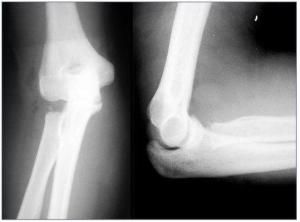

橈骨頭骨折橈骨頭骨折主要臨床表現是肘關節功能障礙及肘外側局限性腫脹和壓痛。尤其前臂鏇後功能受限最明顯。拍攝肘關節前後位和側位X線片可以診斷並能確定骨折類型。骨折的分類法能夠代表損傷程度,並可提供選擇治療方法的依據。必要時可做雙側對比攝片,藉此鑑別。

橈骨頭骨折有Mason分類、Keonconen分類、Morrey分類等。其中Mason分類為大家所接受:

Ⅰ型:為線狀骨折,即無移位型骨折,骨折線可通過橈骨頭邊緣或呈劈裂狀。

Ⅱ型:為有移位的骨折,有分離的邊緣骨折。

Ⅲ型:為粉碎型骨折,移位或無移位或呈塌陷性骨折。

Ⅳ型:為橈骨頭骨折伴有肘關節脫位。

外傷史,肘關節功能障礙及肘外側局限性腫脹和壓痛。尤其前臂鏇後功能受限最明顯。X線能確診骨折及分型。

肘關節正側位X線片和三維CT能夠顯示骨折及分型。